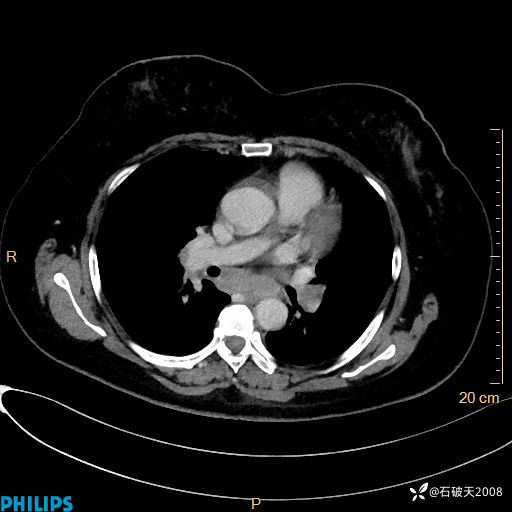

肺结节病?纵膈型肺癌?淋巴瘤?有点意思,欢迎围观

女 52岁 主 诉:咳嗽10余天,咳痰2天。

现病史:10余天前无明显诱因出现咳嗽,呈阵发性干咳,伴咽喉部发痒,无咽痛,无咳痰,无鼻塞、流涕、打喷嚏,无发热、畏寒、寒颤,无头痛、头晕,无胸闷、胸痛,无反酸、烧心,无腹痛、腹泻,无尿频、尿急,无皮疹等,在当地诊所求治,给予口服药物治疗(具体不详),病情无好转。遂在当地社区卫生服务中心开具口服药物治疗(具体不详),疗效欠佳。2天前出现咳痰,在我院门诊求治,行胸部CT提示肺部感染,建议住院,患者要求口服药物治疗,目前仍咳嗽、咳白色粘痰,白天量多,夜间自觉喉部喘鸣音,遂再次来院就诊,以“肺部感染”为诊断收入院。发病以来,神志清,精神可,饮食可,夜间睡眠差,大小便正常,近期体重无明显变化。

动脉期